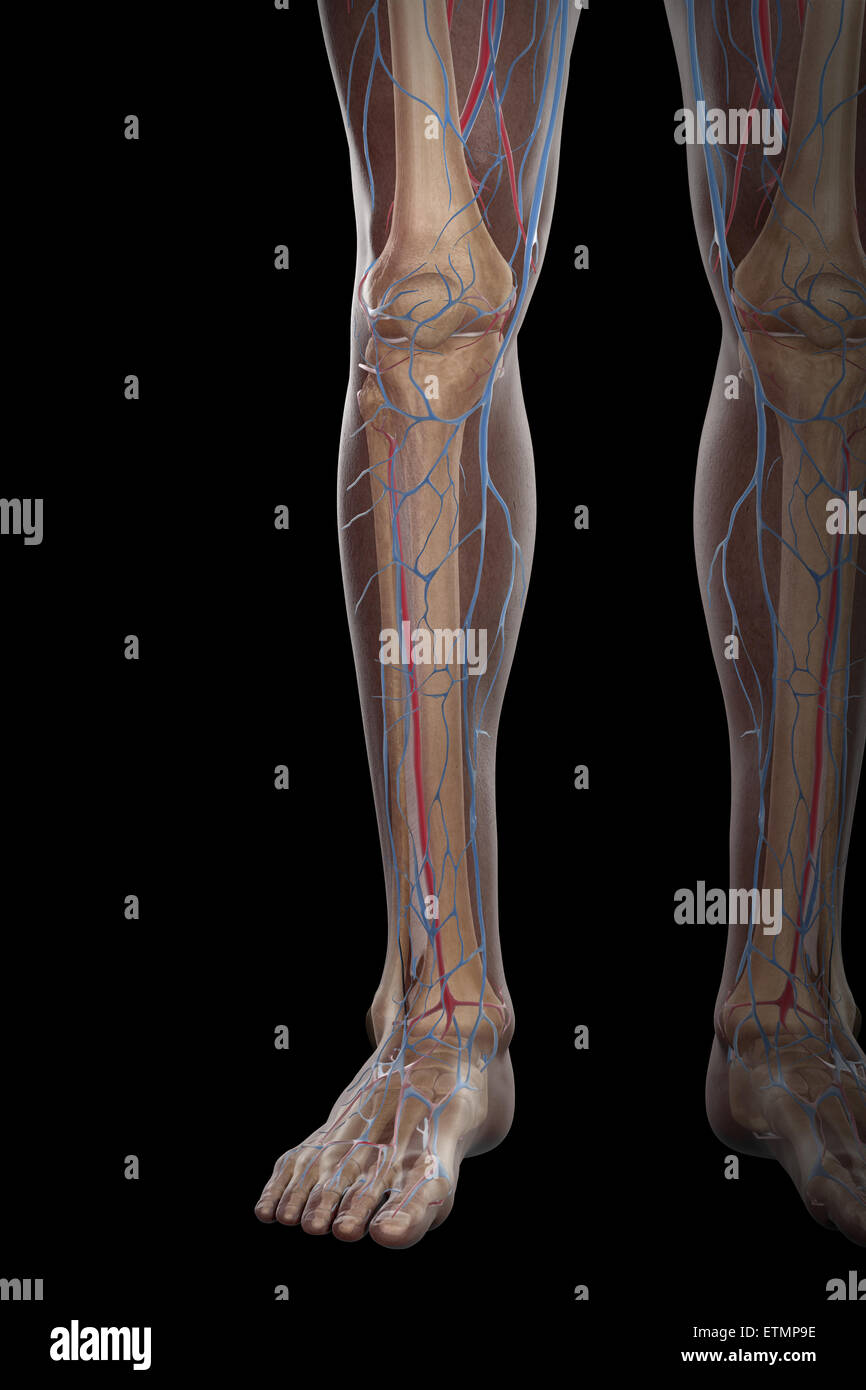

RMETMN27–Darstellung der Blutversorgung und Skelett-Struktur der Unterschenkel, durch die Haut sichtbar.

RMETMNMF–Darstellung der Blutversorgung und Skelettsystem an den Unterschenkeln, durch die Haut sichtbar.

RMETMP9E–Darstellung der Blutversorgung und Skelett-Struktur der Unterschenkel, durch die Haut sichtbar.